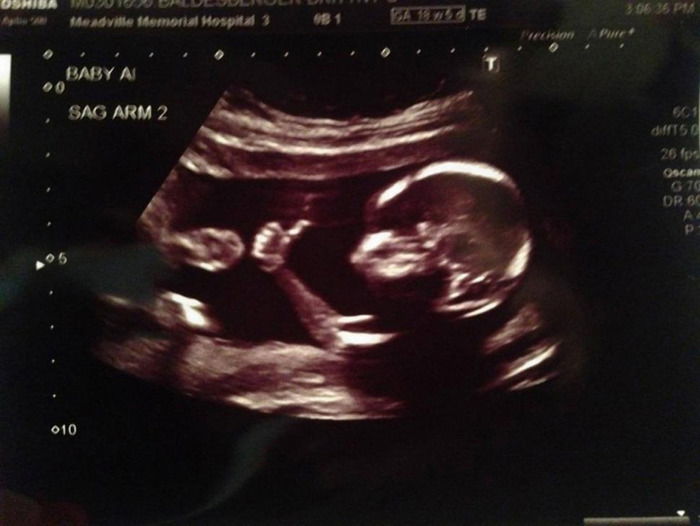

רוצה לייק? תמונה המתעדת צילום אולטראסאונד של עובר במעי אימו, הפכה בימים האחרונים ללהיט ויראלי ברשתות החברתיות, וזאת משום שהעובר נראה בה כשהוא מחזיק באצבעו בדומה לתנועת ה"לייק" המוכרת של פייסבוק.

העובר שמתועד בתמונה הוא בסך הכל בן 18 שבועות, וצילום האולטראסאונד הופק בבית חולים בפנסילבניה, שם נבדקה אמו. חלק מהגולשים ברשת שצפו בתמונה, טענו כי הצליחו לזהות בה תאומים, ולא פעוט אחד.